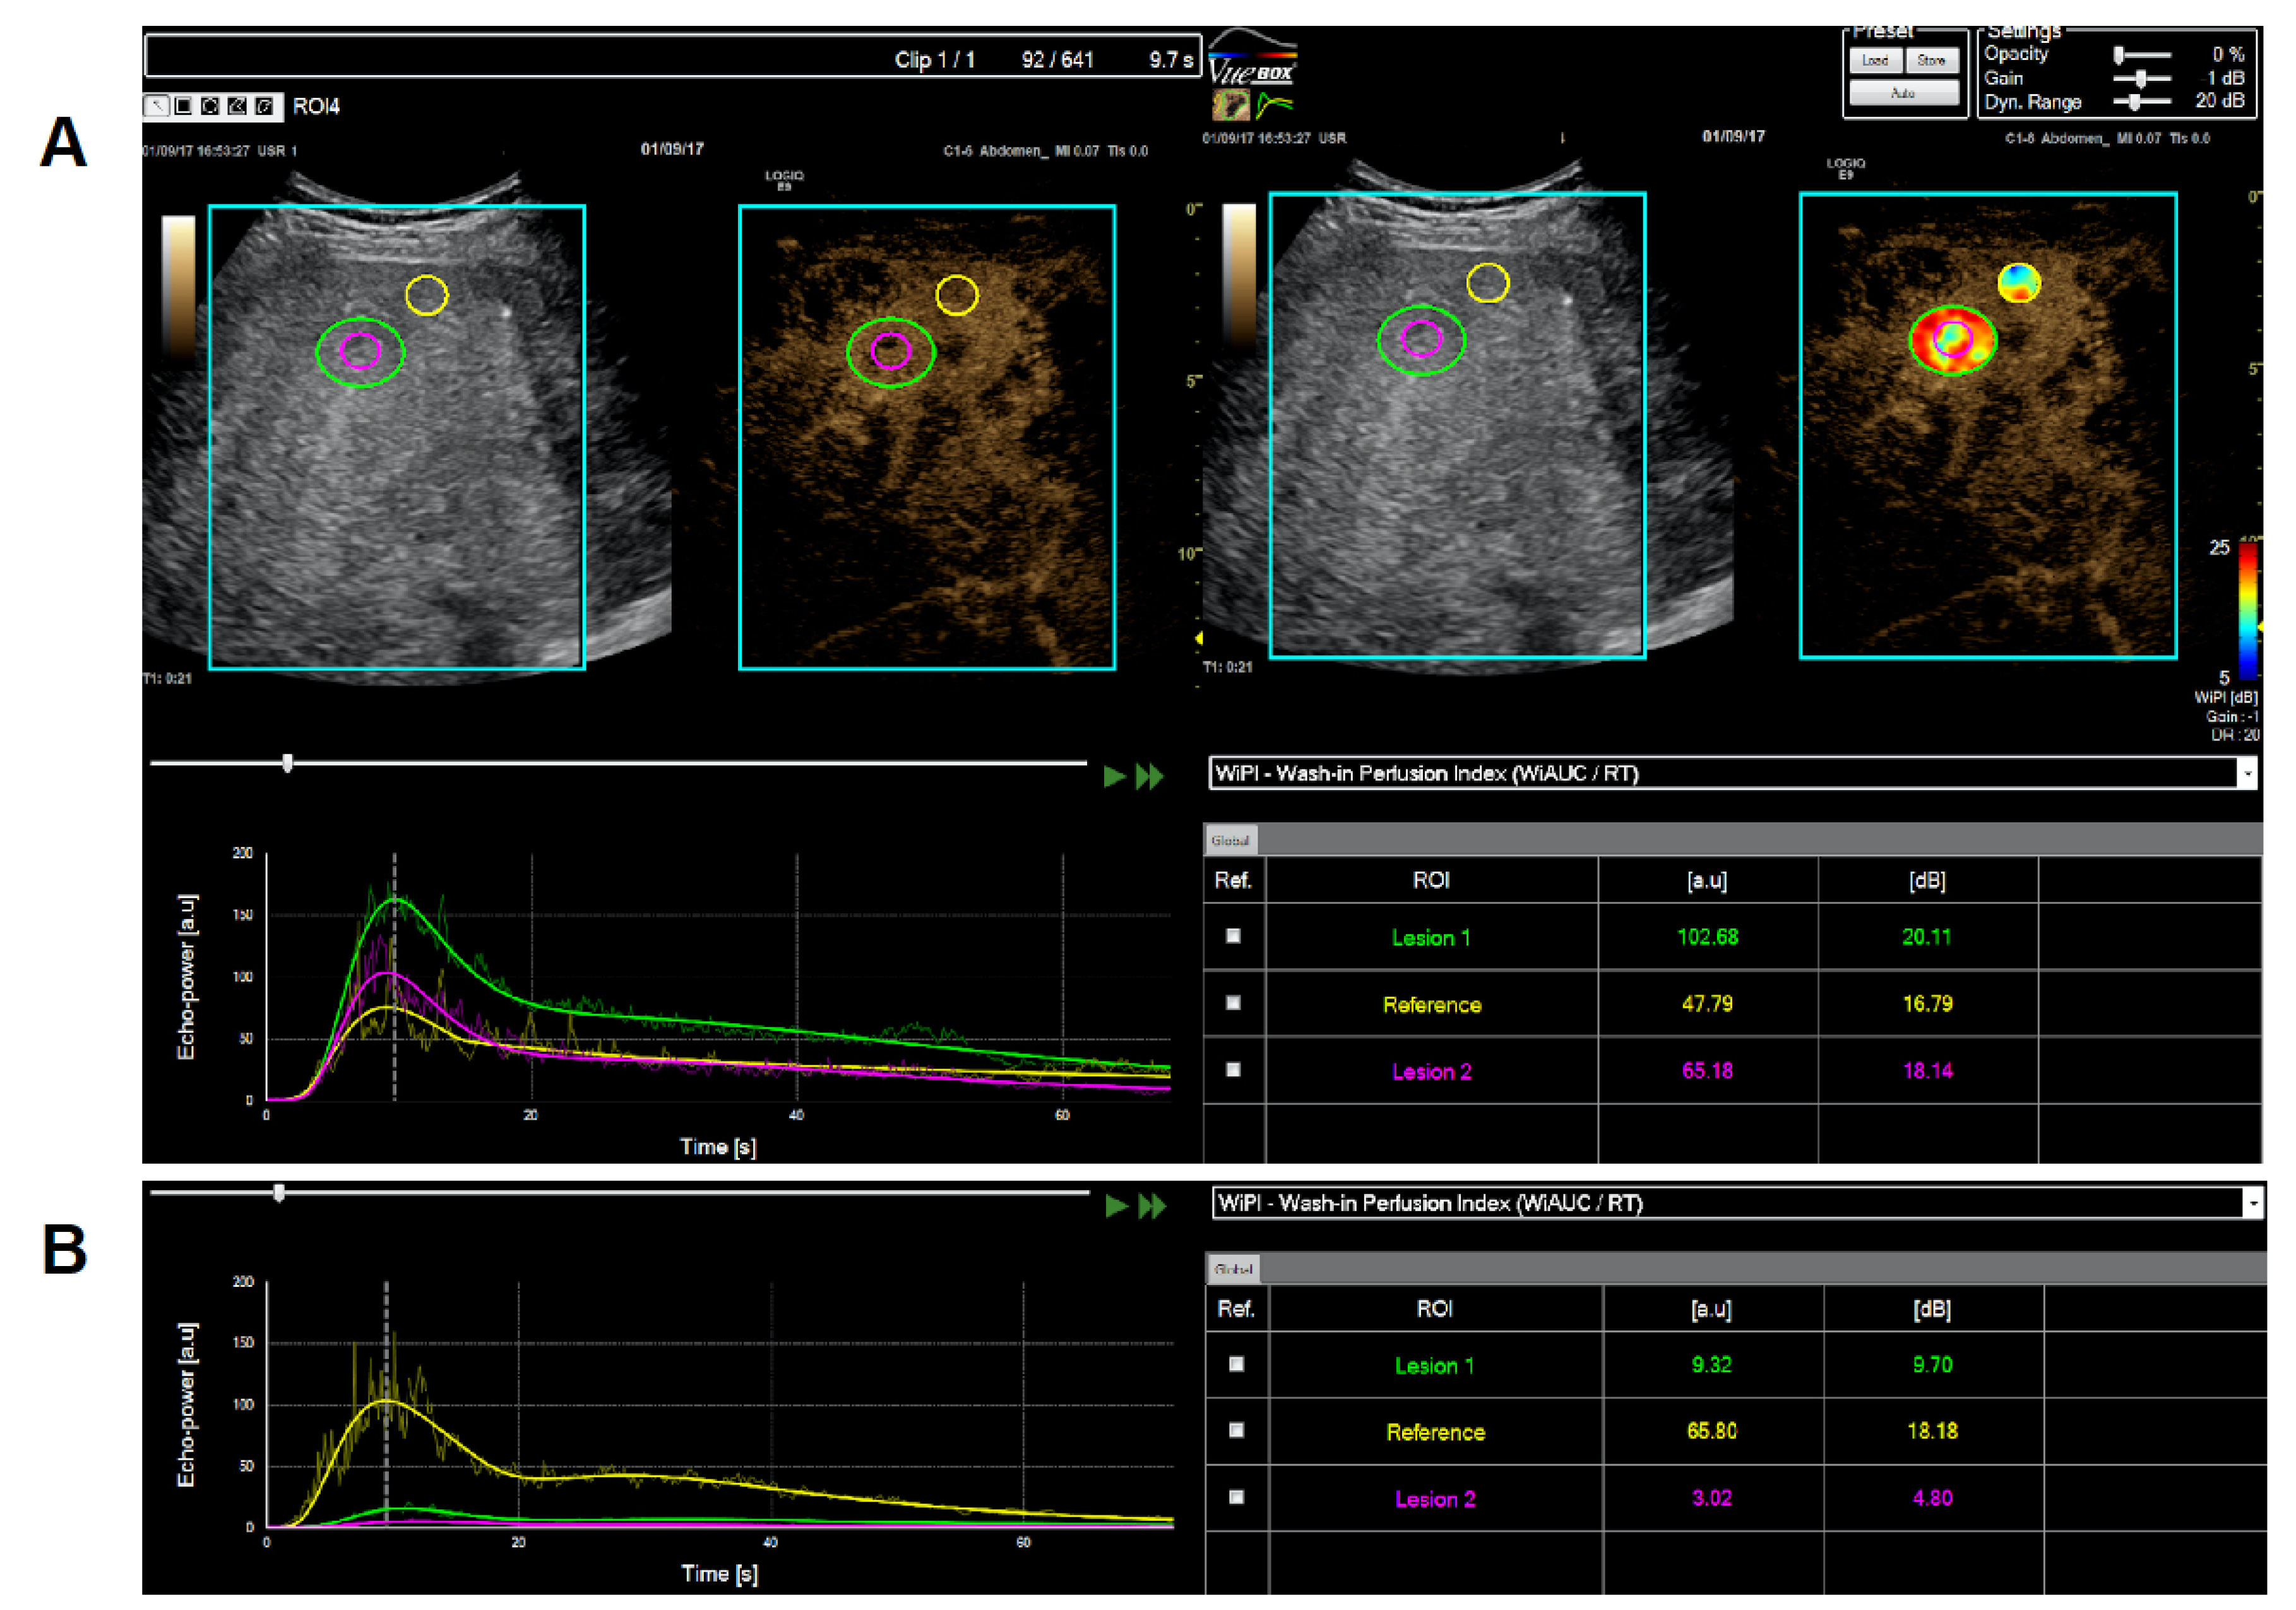

2.3. Dynamic Contrast-Enhanced Ultrasound (CEUS)

| 004 | f | 29 | hepatocellular carcinoma + malignant ascites, multifocal | surgery, Sorafenib, Regorafenib, TACE | 2 | cycle 1: 1.5 cycle 2: 2.0 | good tolerability, no DLT | I: hypointense areas in liver lesions upon therapy (sonography) O: RECIST PD; Q: n.c. |

| 020 | m | 19 | desmoplastic small/round cell tumor, metastatic | VIDE, VAI, Temodal/Irinitecan, | 2 | cycle 1: 3.0 cycle 2: 3.0 | good tolerability, no DLT | I: hypointense areas in liver lesions upon therapy (sonography) O: RECIST PD Q: improved under therapy |